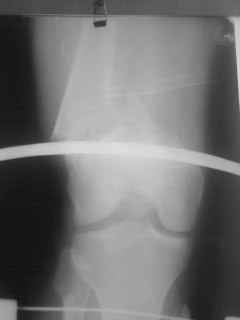

Уважаемые коллеги, прооперирована пациентка антеградным штифтом Остеомед, костная пластика не проводилась. Выбранный штифт по каналу бедренной кости на фоне отсутствия переднего кортикала в канале не центрируется. Технически неприятно, отсутствие передней и внутреннебоковой стенки до зоны мыщелков сильно затрудняло репозицию. Получилась вот такая картина. После стабилизации - очевидное повреждение ПКС и боковая нестабильность. В общем и далее будет чем заняться. Нам и в дальнейшем будет очень интересно мнение коллег.

НО> Получилась вот акая картина.

Молодцы, здорово получилось. Как ввдили самый дистальный винт? Надколенник не мешал?